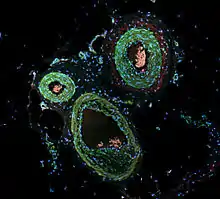

Immunofluorescence is a technique used for light microscopy with a fluorescence microscope and is used primarily on microbiological samples. This technique uses the specificity of antibodies to their antigen to target fluorescent dyes to specific biomolecule targets within a cell, and therefore allows visualization of the distribution of the target molecule through the sample. The specific region an antibody recognizes on an antigen is called an epitope.[1] There have been efforts in epitope mapping since many antibodies can bind the same epitope and levels of binding between antibodies that recognize the same epitope can vary.[2] Additionally, the binding of the fluorophore to the antibody itself cannot interfere with the immunological specificity of the antibody or the binding capacity of its antigen.[3] Immunofluorescence is a widely used example of immunostaining (using antibodies to stain proteins) and is a specific example of immunohistochemistry (the use of the antibody-antigen relationship in tissues). This technique primarily makes use of fluorophores to visualise the location of the antibodies.[4]

Immunofluorescence can be used on tissue sections, cultured cell lines, or individual cells, and may be used to analyze the distribution of proteins, glycans, and small biological and non-biological molecules. This technique can even be used to visualize structures such as intermediate-sized filaments.[5] If the topology of a cell membrane has yet to be determined, epitope insertion into proteins can be used in conjunction with immunofluorescence to determine structures.[6] Immunofluorescence can also be used as a "semi-quantitative" method to gain insight into the levels and localization patterns of DNA methylation since it is a more time-consuming method than true quantitative methods and there is some subjectivity in the analysis of the levels of methylation.[7] Immunofluorescence can be used in combination with other, non-antibody methods of fluorescent staining, for example, use of DAPI to label DNA. Several microscope designs can be used for analysis of immunofluorescence samples; the simplest is the epifluorescence microscope, and the confocal microscope is also widely used. Various super-resolution microscope designs that are capable of much higher resolution can also be used.[8]

Secondary (indirect) immunofluorescence uses two antibodies; the unlabeled first (primary) antibody specifically binds the target molecule, and the secondary antibody, which carries the fluorophore, recognizes the primary antibody and binds to it. Multiple secondary antibodies can bind a single primary antibody. This provides signal amplification by increasing the number of fluorophore molecules per antigen.[10] This protocol is more complex and time-consuming than the primary (or direct) protocol above, but allows more flexibility because a variety of different secondary antibodies and detection techniques can be used for a given primary antibody.[10]